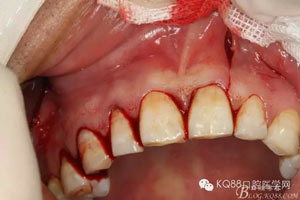

圖3.局部麻醉下,行唇側(cè)21垂直切口+齦溝內(nèi)水平切口